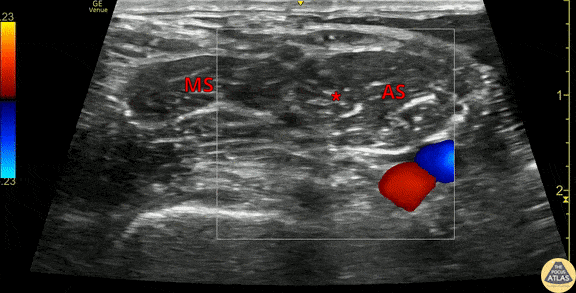

This clip demonstrates the anatomy of the brachial plexus in the interscalene groove. The anterior scalene (AS) and middle scalene (MS) muscles are seen, with the brachial plexus nerve roots (*) seen in the interscalene groove. Color doppler is used to highlight the carotid artery (red) and internal jugular vein (blue) which lie medial/anterior to the brachial plexus. Color doppler is also useful to verify that the brachial plexus nerve roots are not lying deep to other blood vessels. Dr. Michael Heffler, PGY3 Denver Health Residency in Emergency Medicine